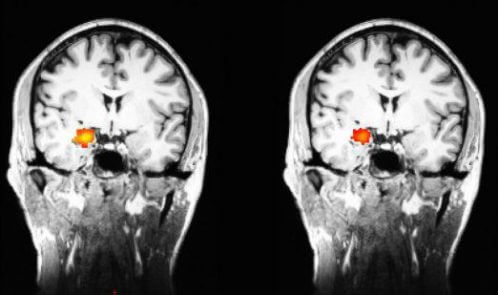

دزبوردز در پژوهش خود از fMRI بهره گرفت که با این روش نه تنها عکس هایی از مغز تهیه کرد بلکه گزارشات رخداد فعالیت مغزی طی اسکن نیز ثبت گردید. در سال ۲۰۱۲ او شرح داد که تغییرات در فعالیت مغز در افراد مورد آزمایش که مراقبه را فراگرفته بودند حتی هنگامی که آن ها در حال مراقبه نبودند، به طور ثابت حفظ شده بود. دزبوردز، اسکن هایی از قبل و بعد مغز افراد مورد آزمایش که مراقبه را طی یک دوره دو ماهه فراگرفته بودند، تهیه کرد.او این اسکن ها را نه تنها در زمان مراقبه بلکه زمانی که کیس های مورد مطالعه در حال انجام کارهای روزمره خود بودند نیز تهیه کرد.

با این حال در اسکن ها هنوز تغییرات درالگوهای فعالیت های مغزی نمونه های مورد آزمایش از ابتدا تا آخر مطالعه قابل تشخیص بود، اولین بار چنین تغییری در بخشی از مغز به نام آمیگدال شناسایی شد.